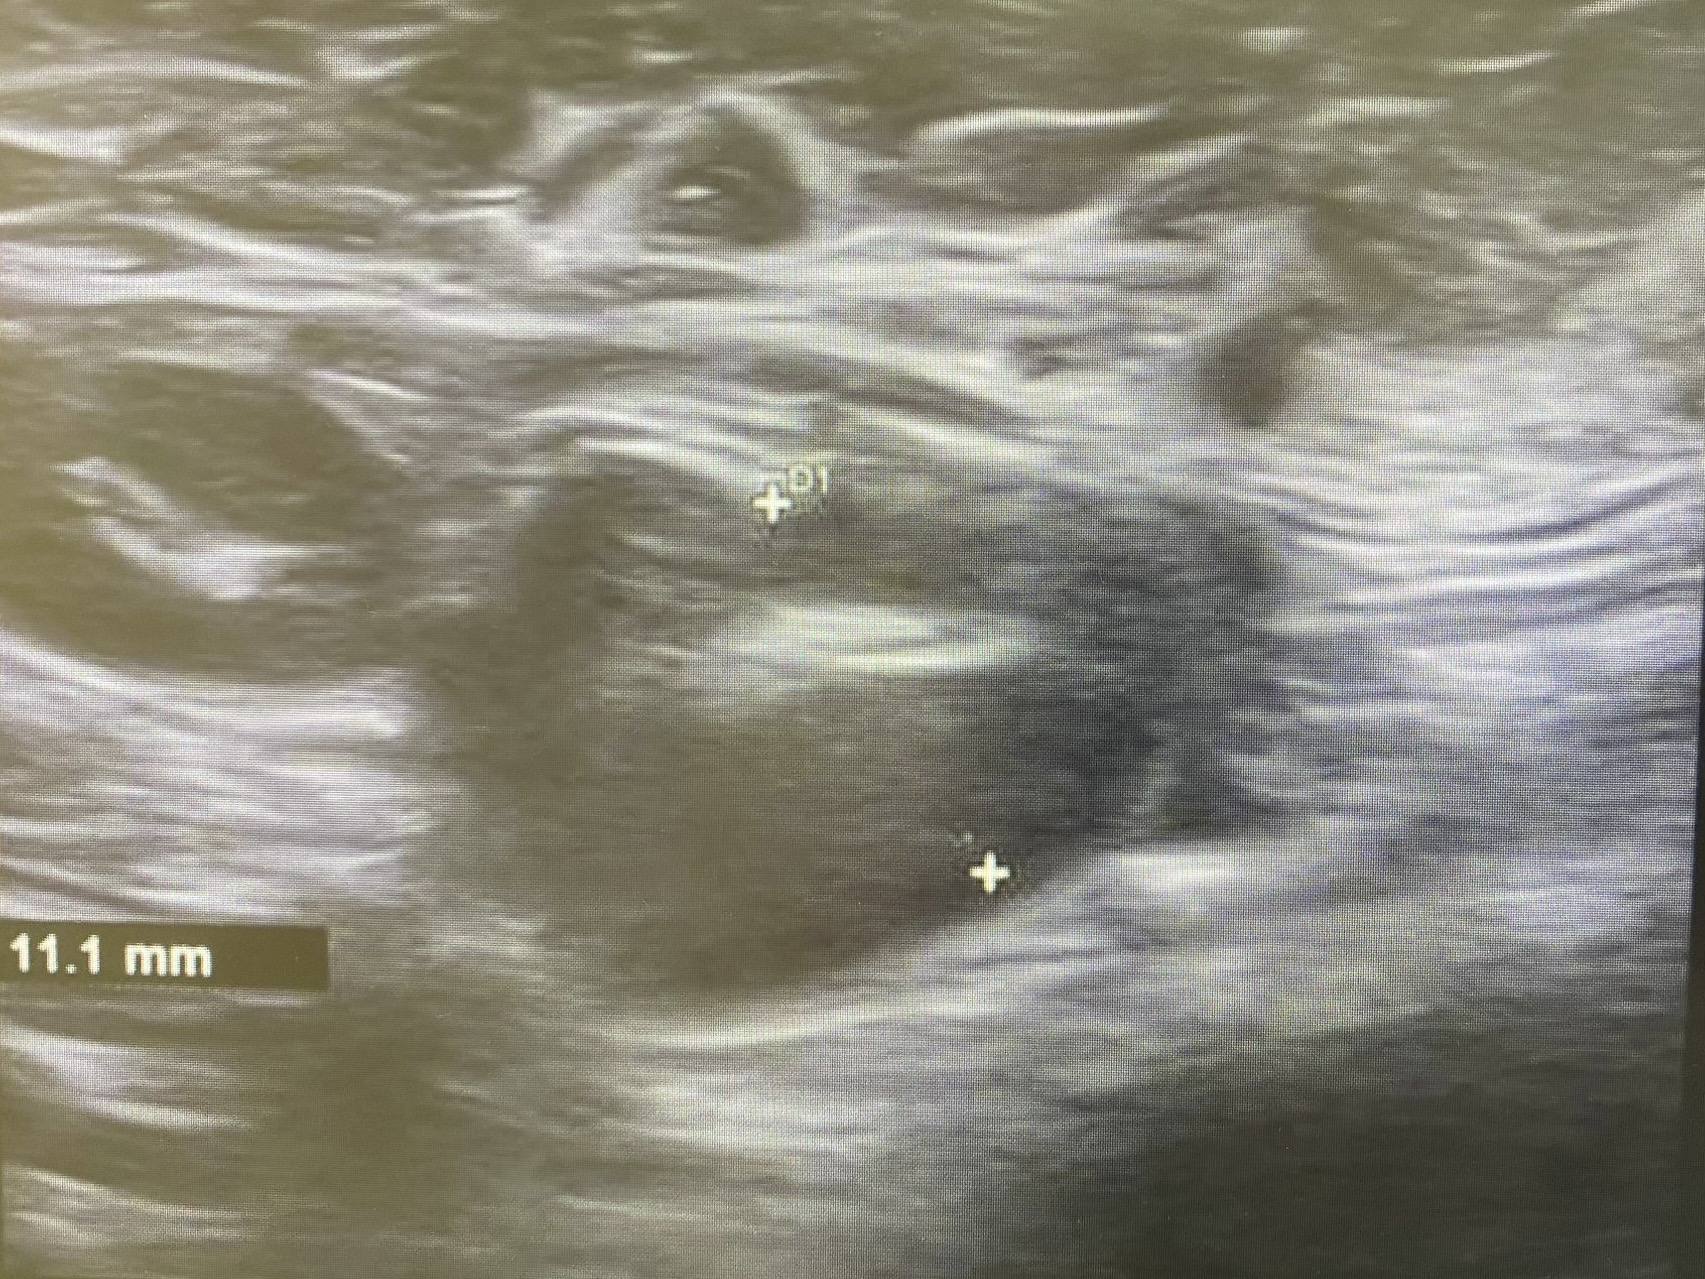

Ecografía: Valoración de adenopatías para acercamiento diagnóstico (típicas/atípicas).

Adenopatías patológicas, algunas redondeadas, con eje anteroposterior > 1 cm, parénquima homogéneo, cortical engrosada aunque con hilio respetado.

Ecografía mamas: quistes y nódulos hipoecogénicos bilaterales.

Ecografía axilar: múltiples adenopatías con eje corto > 2 cm y cortical engrosada.